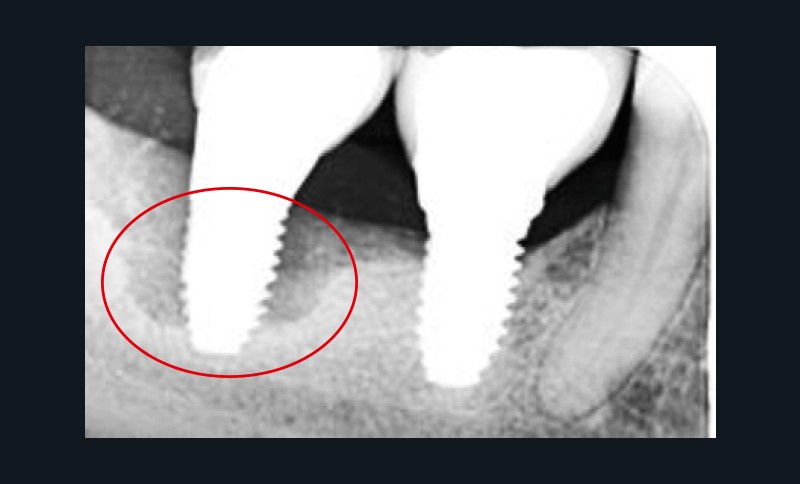

La péri-implantite

La plaque bactérienne (biofilm) pénètre et envahit les tissus muqueux autour des implants dentaires (fig. 3). S’installent une inflammation de la muqueuse péri-implantaire et la perte progressive et asynchrone du tissu osseux [4]. La péri-implantite survient au cours des premières années de mise en fonction de l’implant [4] et en l’absence de traitement, la maladie progresse (fig. 4) de manière non linéaire et rapide [4, 7].